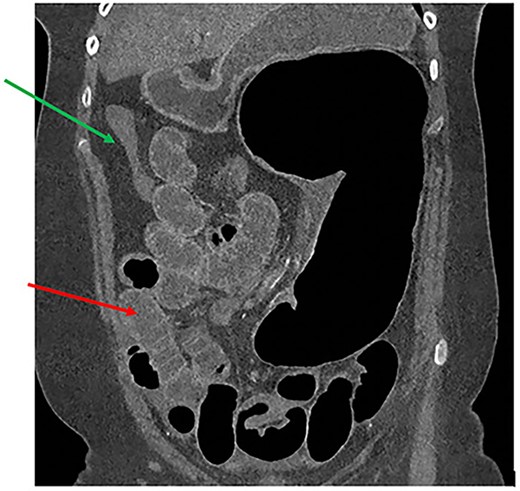

A 61-year-old female with known Marfan Syndrome was admitted to the emergency department with 3-day history of abdominal pain, nausea, vomiting and bowels not opening. Past medical history included three previous episodes of Type A aortic dissection, recent aortic root and ascending aorta replacement alongside bioprosthetic aortic valve replacement. She was an ex-smoker and usually independent at home. On presentation, the patient was haemodynamically stable and apyrexial. Biochemical results were unremarkable except for a Lactate dehydrogenase (LDH) of 309 and a C-reactive protein (CRP) of 101. On examination, she had a diffusely tender and distended abdomen, without signs of peritonism. An erect chest X-ray shows left pleural effusion with a dilated aortic root (Fig. 1). A computed tomography (CT) of thorax, abdomen and pelvis was requested, which demonstrated a caecal volvulus with a dilated cecum of 8.8 cm and upstream small bowel dilatation with air fluid levels, and a chronic aortic dissection extending from the ascending thoracic aorta to the common iliac (Figs 2–4). Following consultation between radiologists, cardiothoracic surgeons and general surgeons, she underwent an emergency laparotomy and right hemicolectomy with side-to-side ileocolic anastomosis. Intraoperatively, the caecal volvulus, comprising a dilated ascending colon measuring up to 10 cm, was delivered and resected along with its mesentery. The patient was admitted to the intensive care unit post-operatively for close blood pressure monitoring and control and stepped down to level 3 wards on day-2 post-operation. Her operation was complicated by a small infected wound haematoma thatwas managed with a 5-day course of ciprofloxacin. A CT of the abdomen and pelvis to investigate a rising CRP on day-9 revealed a subcapsular liver haematoma thath was managed conservatively. The patient was discharged 12-days post-operatively. Histology from the resected colon showed evidence of ischaemia in keeping with a closed loop obstruction such as caecal volvulus. There was also an incidental T1 N0 colonic tumour arising from a sessile serrated polyp and two other serrated polyps. A colonoscopy to inspect the remaining colon has been arranged.

CT thorax, abdomen and pelvis coronal view demonstrating a distended, twisted caecum, caecum in the left upper quadrant, small bowel distension (red arrow) and a decompressed ascending colon (green arrow).